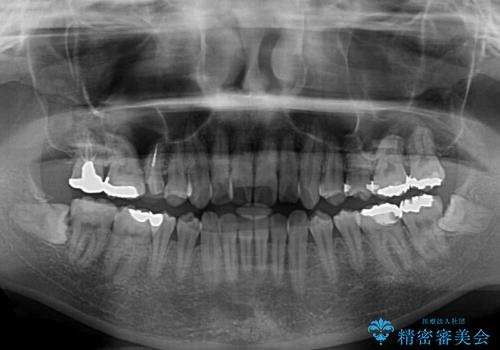

- 捻れた前歯が飛び出しており、口が閉じにくいとのことで来院された患者様です。

出っ歯というわけではないものの、前歯の捻転により口唇が押し出されている状態でした。

親知らずを抜去し、歯列全体を後方に移動させつつ、IPR(歯と歯の間を削る)でスペースを獲得し、インビザラインを用いて叢生を解消しながら前歯の突出を改善することとしました。